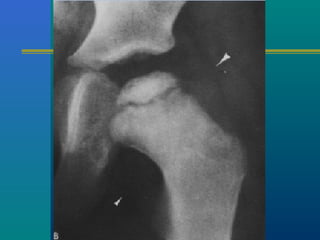

PERTHES DISEASE

Common problem

4 – 12 years of age

Male > female (4:1)

Low socioeconomic status

Etiology

Exact etiology – unknown

Current theory – vascular

embarrassment

Increased intra-osseous

pressure

This results in avascular

necrosis of the capital

femoral epiphysis.

INVESTIGATIONS

X-ray --- AP & FROG LEG

LATERAL

Sclerosis of the epiphysis

Collapse of the epiphysis

Subchondral fracture

MRI – to know the shape

of the cartilage

ARTHROGRAM

ARTHROGRAM

Subchondral fracture

heralds the onset of

clinical Perthes.